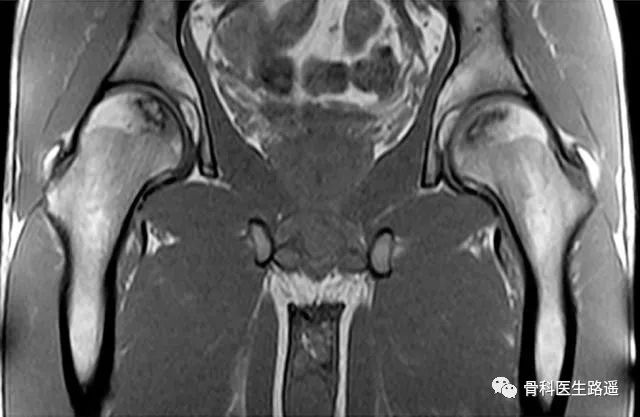

然而,2年后男孩因为右边膝盖疼来医院检查,磁共振(如下图)意外的发现了他患有双侧股骨头坏死。可想而知,与之前长期大量的激素治疗有关(但当时为了保住脊髓,实在不得已)。